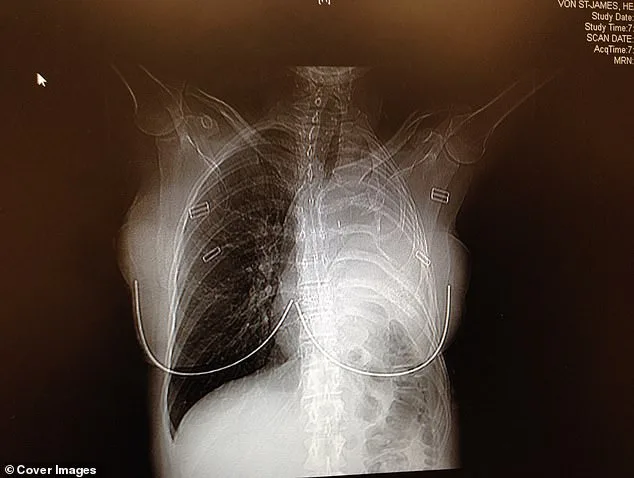

She and her husband flew to Boston to see a specialist who performed a radical surgery. In February 2006, doctors removed her left lung, a rib, the lining of her heart and part of her diaphragm, replacing them with surgical Gore-Tex. The tumor was excised with clean margins. No visible cancer remained. "My mind was spinning and I couldn't breathe," Von St James said. "I started to have a panic attack in that room while they were explaining what mesothelioma was. I began crying and had to leave the room." It was the hardest day of her life. She felt incredibly alone and scared.

In February 2006, doctors removed her left lung, the rib above it, the lining of her heart and part of her diaphragm. In their place, they used surgical Gore-Tex—the same material used in waterproof clothing—to rebuild parts of her chest. The surgery was a success. Surgeons had excised the tumor with perfect margins, leaving no visible cancer behind. As a precaution, to make sure they removed every bit of cancer, doctors infused warm drugs directly into her chest cavity, rocking her back and forth for an hour to circulate the medicine and kill any remaining cancer cells. "Patients call it the 'shake and bake,'" Von St James said. She endured four rounds of chemotherapy and 30 sessions of radiation. "People say once you survive cancer, everything should be great," she said. "But there are a lot of ongoing physical things that happen after surgeries."